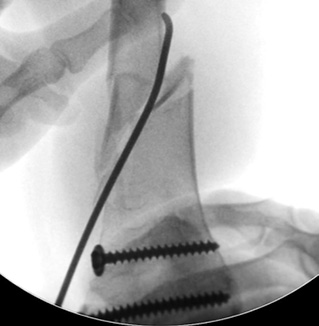

The first stage of the surgery was osteosynthesis of the distal metaepiphysis of left femur by two cannulated cancellous screws of 6.5 mm in diameter with full threading and with washers above and below the growth zone. Next, an attempt at retrograde osteosynthesis of TEN d = 3.0 mm was made from the standard approaches proximal to the growth zone. Due to the extremely low quality of the bone tissue and the comminuted nature of the fracture of metaphyseal zone, the titanium rods broke the cortical layer of the bone at the site of their insertion or perforated the opposite cortical layer (Fig. 4). It was decided to perform antegrade insertion of internal fixation devices. The rod was inserted through the lateral cortical layer of the upper third of femur and brought to the distal metaepiphysis, and then fixed in place with screws. Due to the small size of the distal metaepiphysis, in order to ensure satisfactory fixation, we perforated the growth zone. The distal end of the rod was placed behind the proximal screw and in front of the distal screw before being fixed in the subchondral zone of bone. Osteosynthesis with a second rod was not possible due to the narrow intramedullary canal. Enlarging the canal by drilling was technically impossible without additional surgical access, which would have significantly increased blood loss, volume, and time of surgery (Fig. 5 a).

Fig. 4. Intraoperative radiograph, TEN perforation of the opposite cortical bone layer